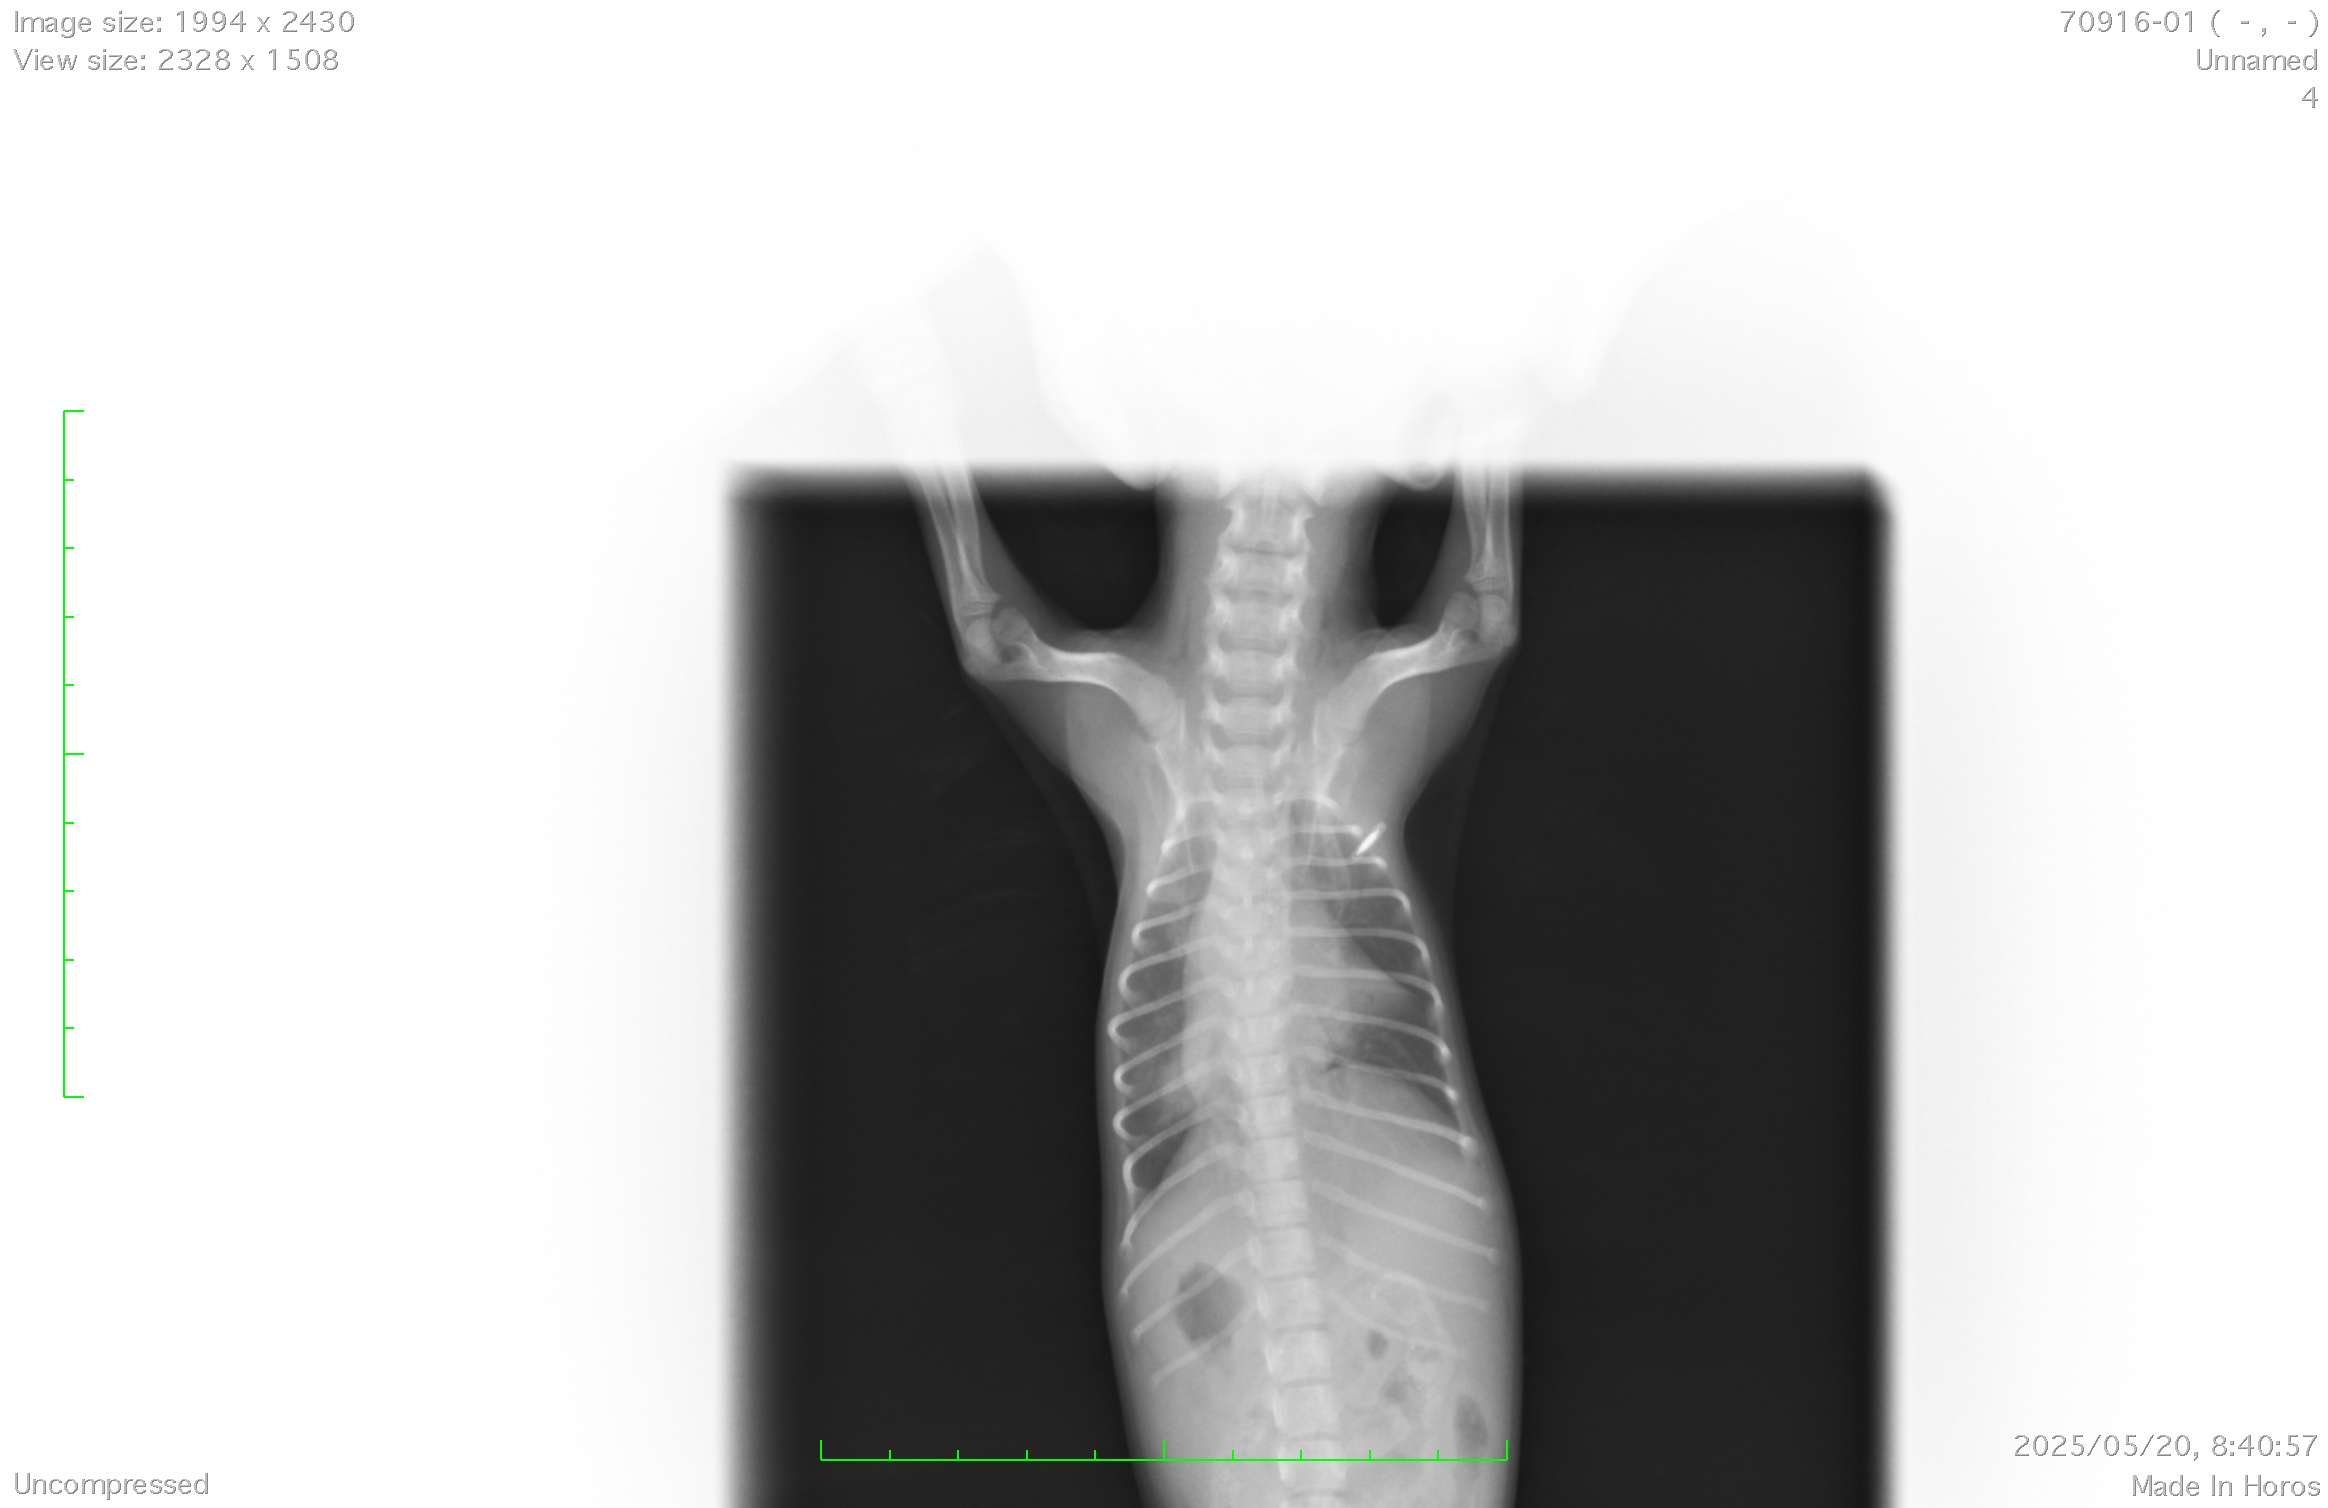

手術の方法や、手術可能かどうかまた現在の治療をどうするかなどことを知るため、超音波(エコー)検査を実施し確定診断します。